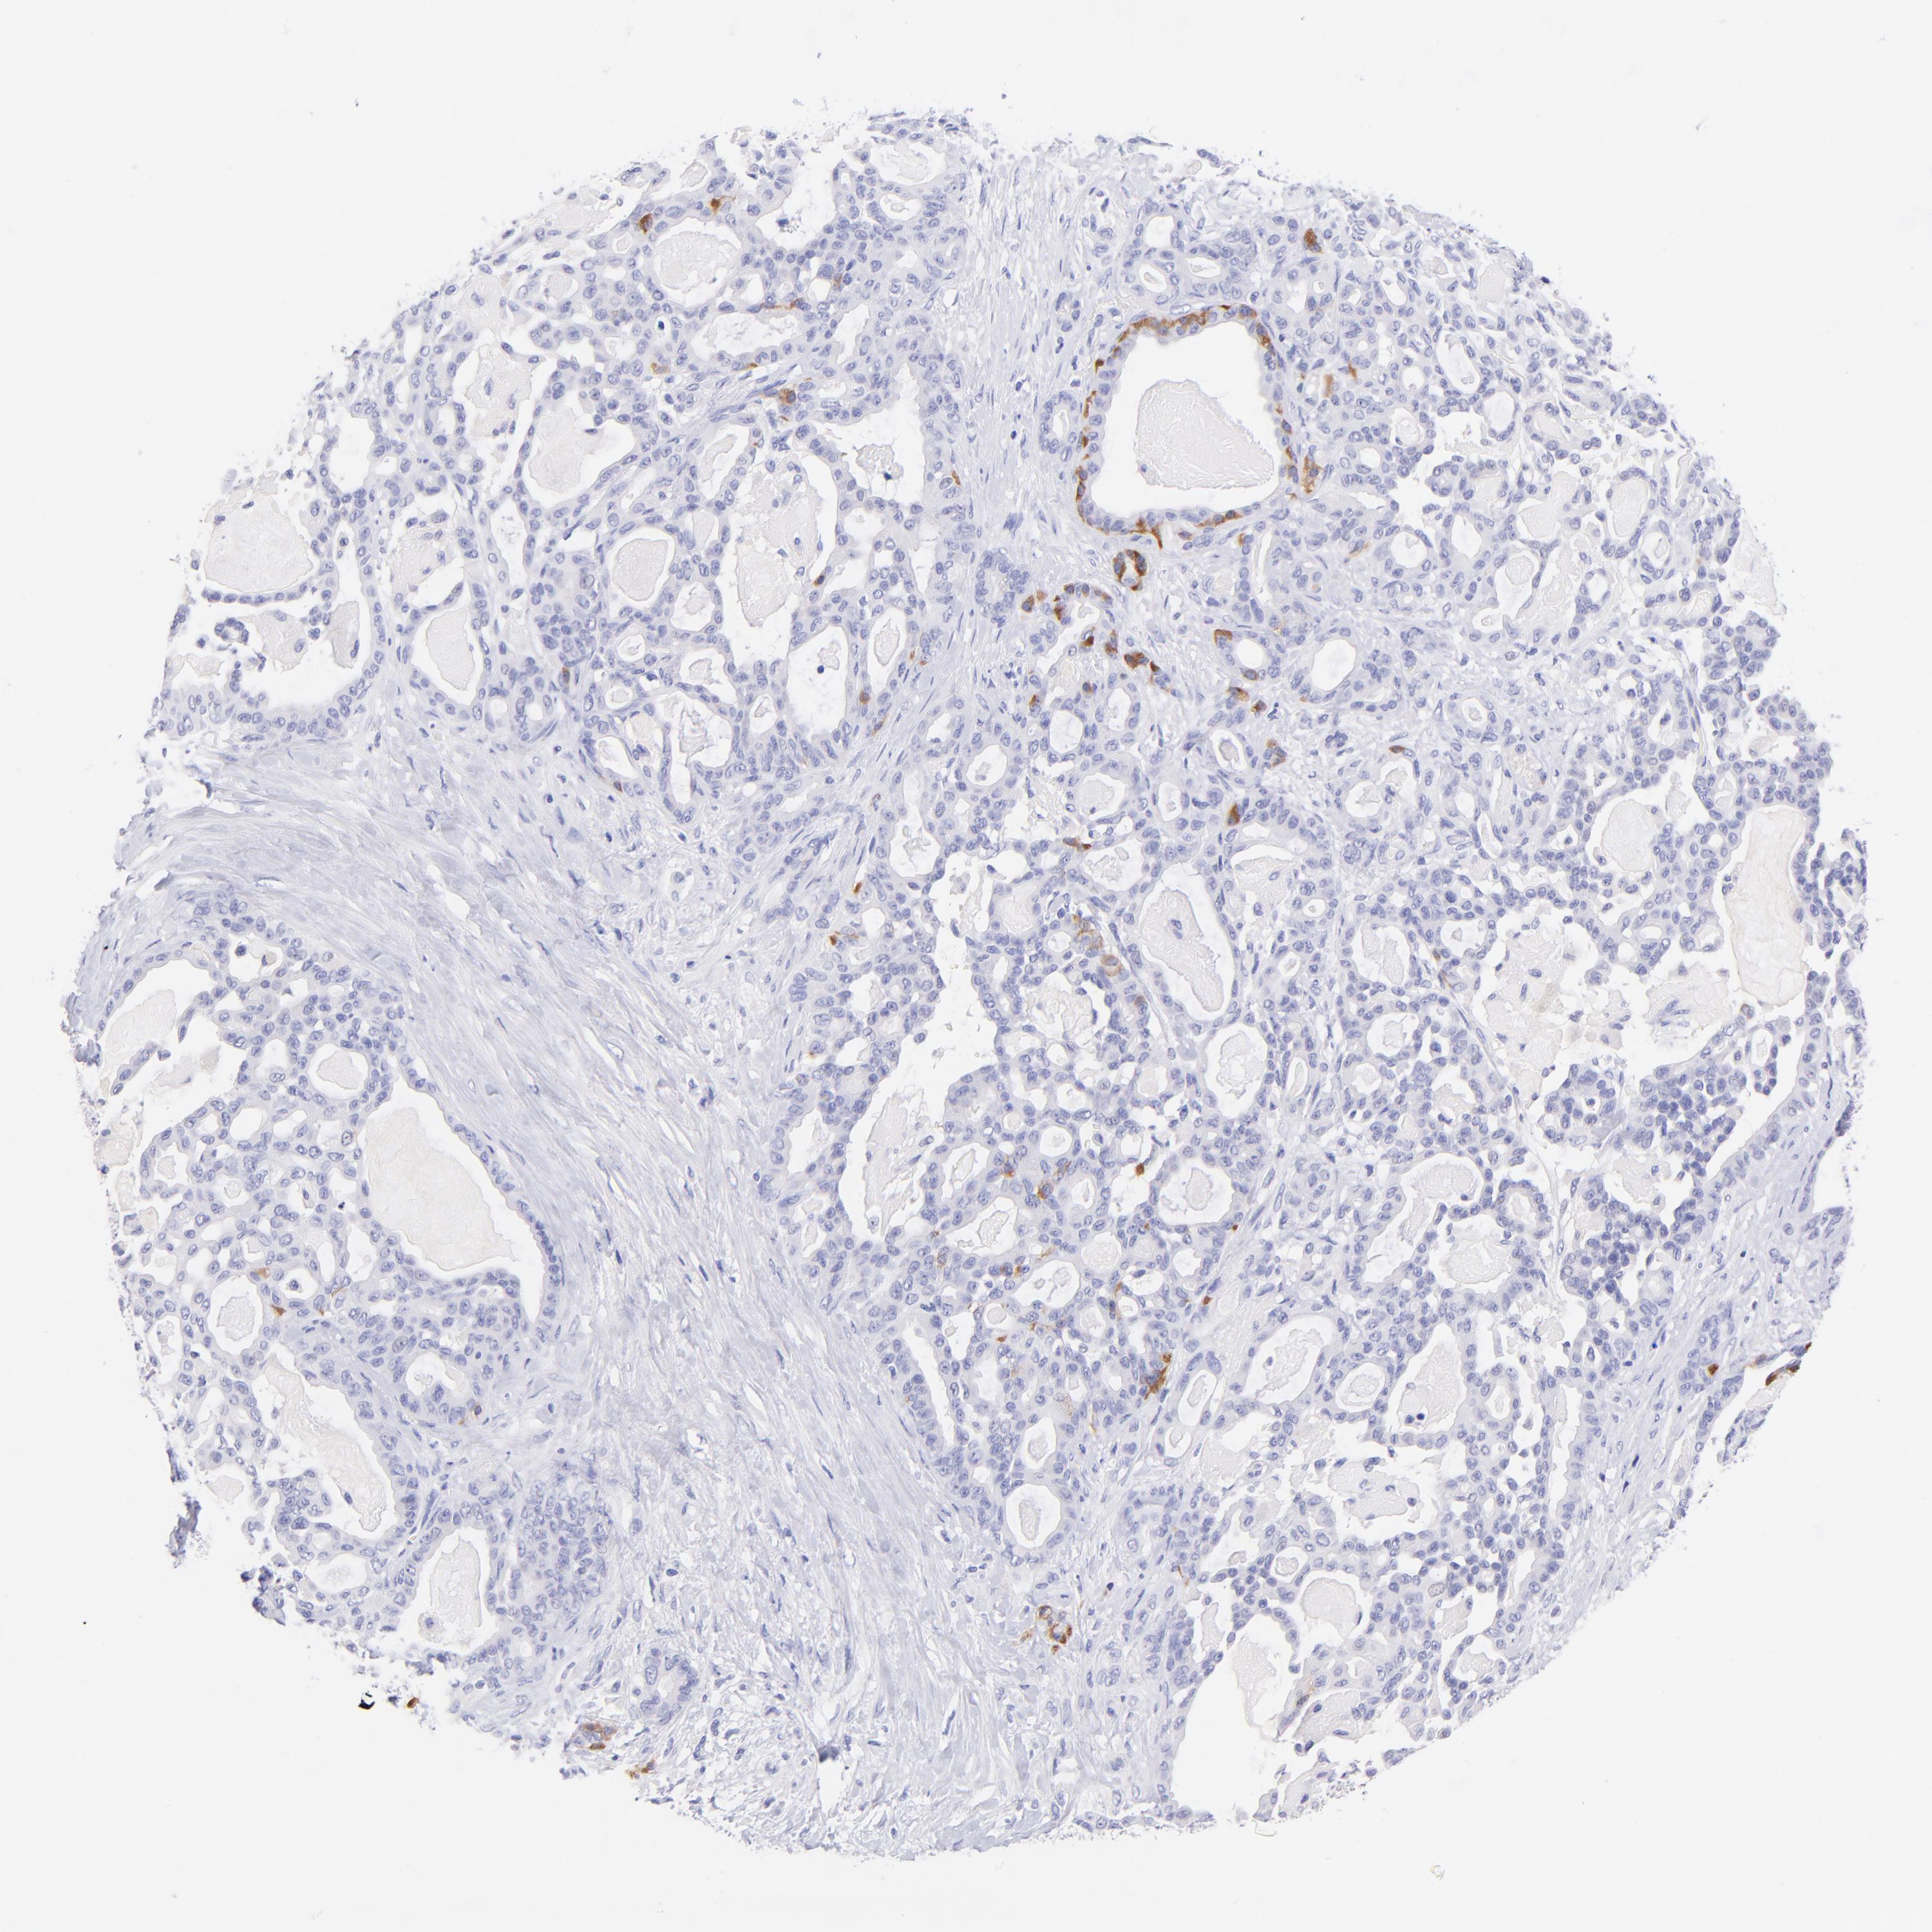

PANCREATIC CANCER - Protein expressioni

A mouse-over function shows sample information and annotation data. Click on an image to view it in a full screen mode. Samples can be filtered based on level of antibody staining by selecting one or several of the following categories: high, medium, low and not detected. The assay and annotation is described here.

Note that samples used for immunohistochemistry by the Human Protein Atlas do not correspond to samples in the TCGA dataset.

Antibody stainingi

Antibody staining in the annotated cell types in the current human tissue is reported as not detected, low, medium, or high, based on conventional immunohistochemistry profiling in selected tissues. This score is based on the combination of the staining intensity and fraction of stained cells.

Each image is clickable and will lead to virtual microscopy that enables deeper exploration of all samples and also displays staining intensity scores, fraction scores and subcellular localization as well as patient and tissue information for each sample.

Antibody HPA003159

Antibody CAB023293